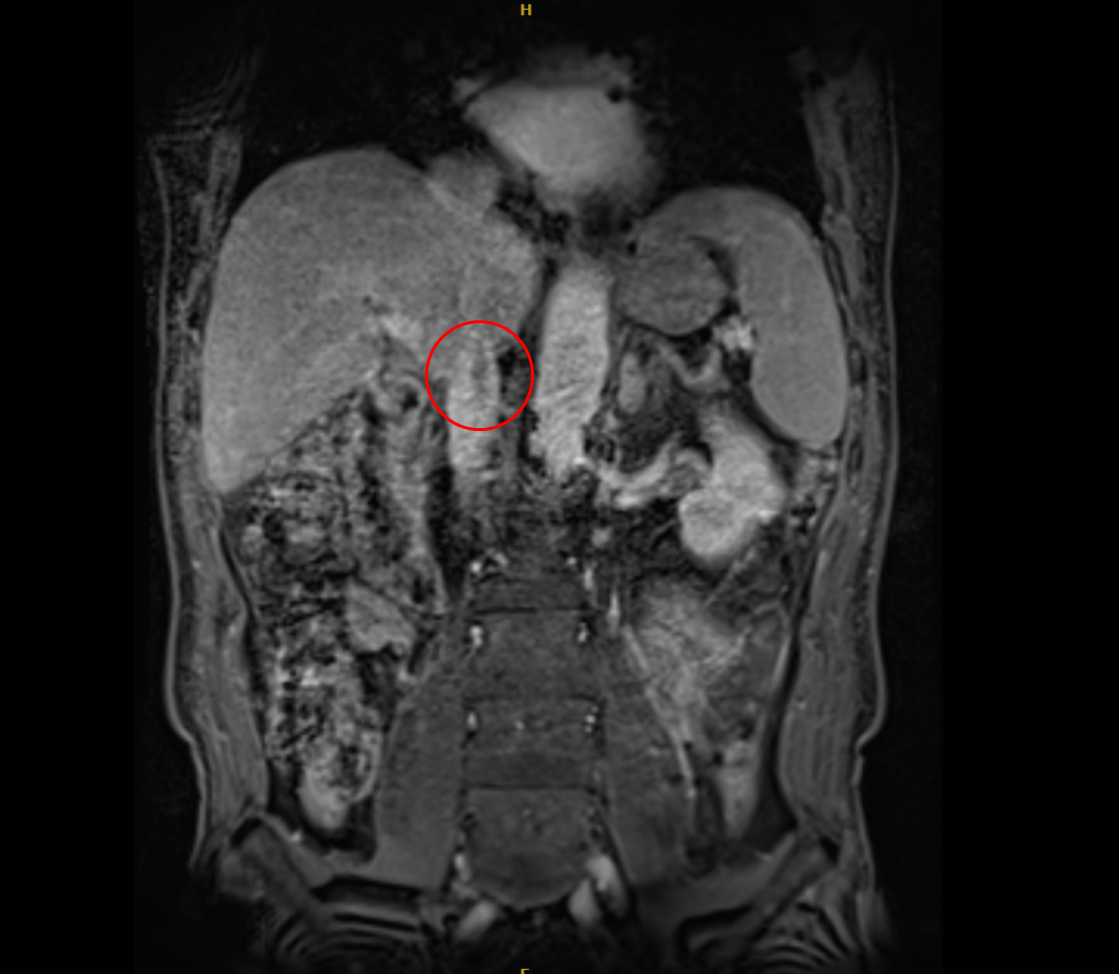

患者磁共振重建影像(红圈内示瘤栓)

肾癌合并下腔静脉瘤栓,本就是泌尿外科领域极具挑战的复杂病例,而这位患者的情况尤为困难——瘤栓已越过肝短静脉,进入膈肌水平以上的下腔静脉,属于MayoIII级,手术风险极高,犹如在血管中“拆弹”。一旦瘤栓脱落,随时可能引发急性肺栓塞,导致患者猝死。此外,患者主动脉和肾动脉严重钙化,加之既往的支架植入史,更让手术难度成倍增加。